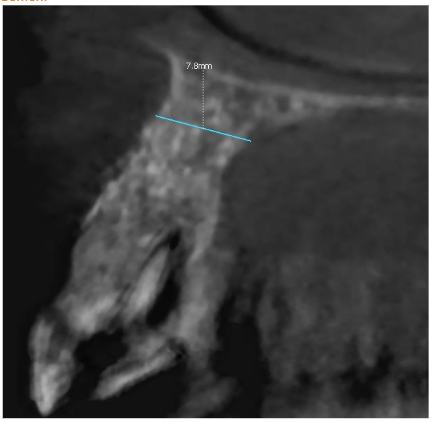

CBCT lateral scan

CBCT after 6 months post-op showed excellent regeneration of both cortical plates in range almost 8.0 mm!